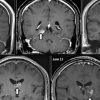

이완구 병역의혹 공개 검증 “차남 전방십자인대 재건수술 확실”

이완구의혹해명 “MRI·엑스레이 촬영도 응할 수 있어”